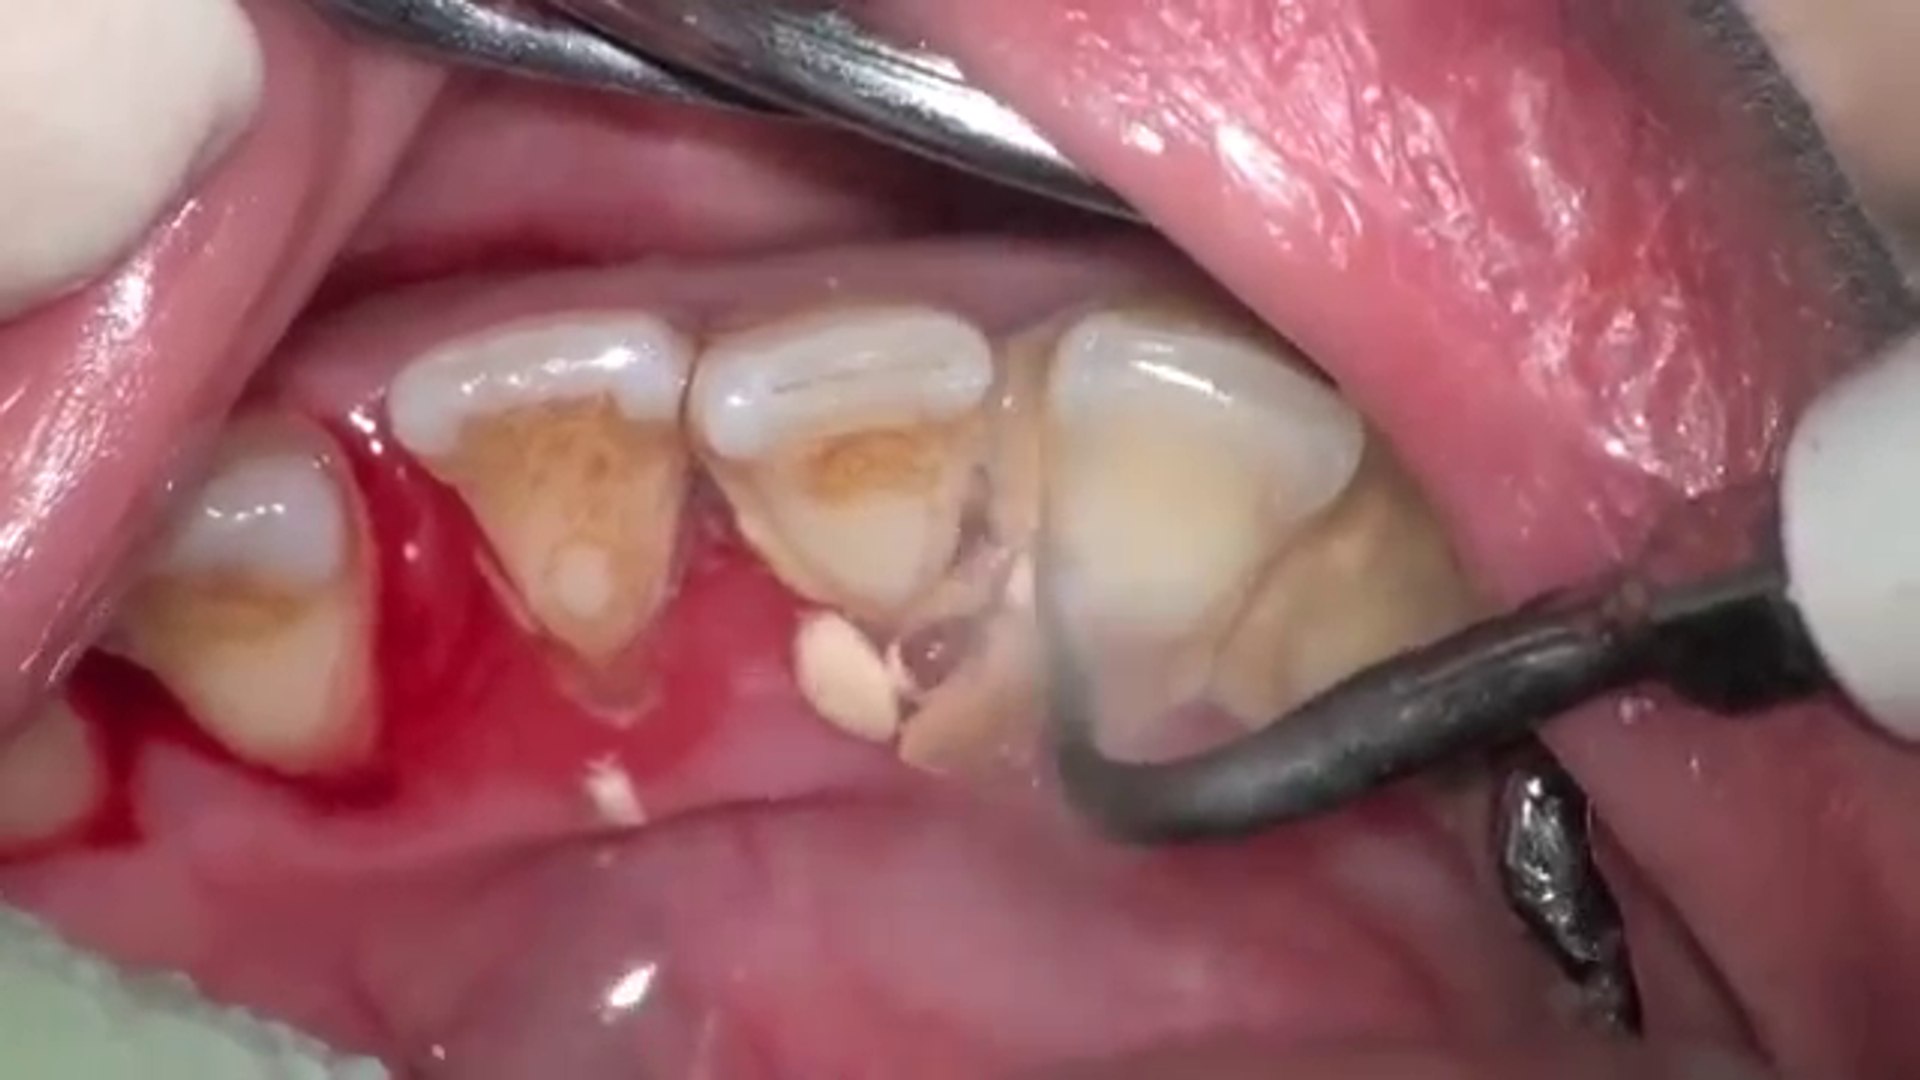

Détartrage du chien sans anesthésie quelles solutions

Web voici le moyen le plus simple d'habituer votre chien à un brossage des. Web le détartrage est l'action consistant à enlever le tartre qui s'est accumulé sur les dents. Web enlever le tartre des dents du chien naturellement, sans anesthésie générale et éviter la.

Web une vraie alternative économique au détartrage chez le vétérinaire détartrage en. Web la conséquence la plus fréquente que le tartre engendre est la mauvaise haleine du chien. Si les dents de votre chien présentent du tartre, montrez.

Web une fois votre chien anesthésié, le vétérinaire utilisera un appareil à. Web chez les animaux, le détartrage est un acte réservé aux vétérinaires. Le 4 février 2021 mon chien yorkshire terrier de 11 ans est mort.